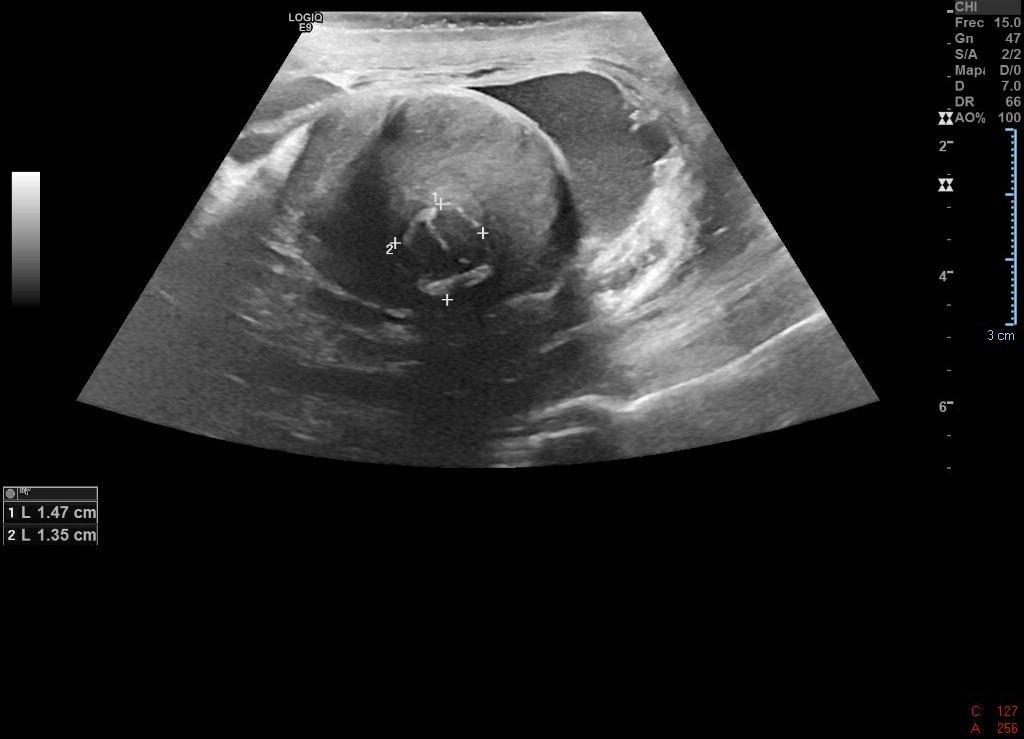

Ecografía de abdomen de Urgencias: se observa gran LOE pélvico abdominal ecogenicidad heterogénea, con hígado aumentado de tamaño y con imágenes hipoecoicas. Uterohidronefrosis derecha.

Igualmente se concluyó el estudio con ecografía de testículo y RNM.